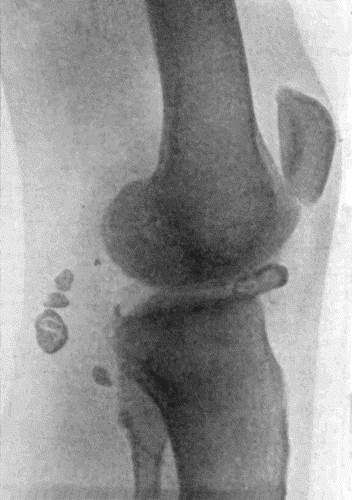

536 166.Radiogram of Multiple Loose Bodies in Knee-joint

540 167.Loose Body from Knee-joint